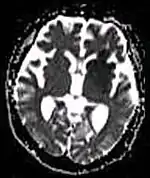

| Diffusion weighted (DWI) | Conventional | DWI | Measure of Brownian motion of water molecules.[80] | High signal within minutes of cerebral infarction (pictured).[81] |

|

| Apparent diffusion coefficient | ADC | Reduced T2 weighting by taking multiple conventional DWI images with different DWI weighting, and the change corresponds to diffusion.[82] | Low signal minutes after cerebral infarction (pictured).[83] |

| |